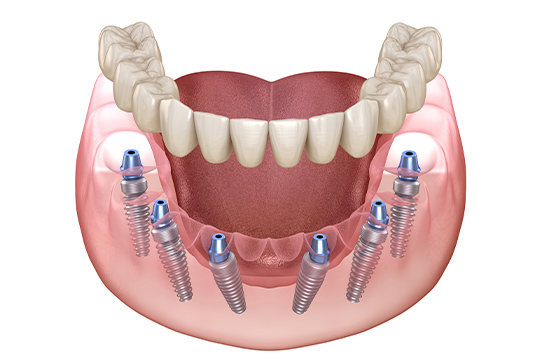

전악 임플란트는 임플란트 틀니보다 씹는 힘이 훨씬 좋습니다.

내 치아처럼 사용이 가능하며

전체 치아 기능의 90% 정도로 회복력이 좋습니다.

일상생활의 불편함을 줄이기 위해

임시치아를 제작하여 사용합니다.

저작과 심미 상태를 확인하며

최종 보철을 위한 준비를 진행합니다.